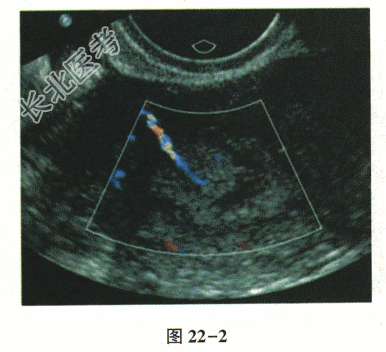

- 单项选择题患者女,36岁, 不规则阴道流血半年余,其子宫超声声像图如图22-1, 图22-2。最可能的诊断是

A、子宫内膜癌

B、子宫内膜息肉

C、子宫绒毛膜癌

D、子宫黏膜下肌瘤

E、子宫内膜不典型增生